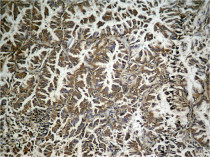

ARG51812 anti-eIF2 alpha phospho (Ser49) antibody IHC-P image

Immunohistochemistry: Paraffin-embedded Human breast carcinoma tissue stained with ARG51812 anti-eIF2 alpha phospho (Ser49) antibody (left) or the same antibody preincubated with blocking peptide (right).